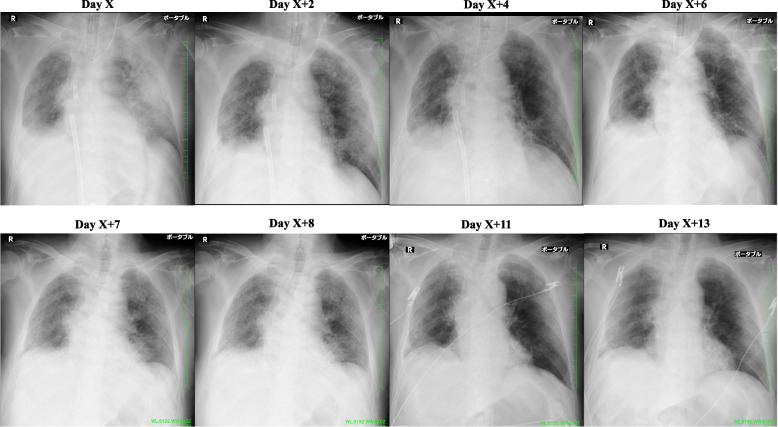

Fig. 2.

X-ray images showing the disease course of interstitial pneumonia in the patient after postoperative readmission to hospital. At the time of introduction of ECMO, bilateral frosted shadows and mild congestive images were detected, partly due to the effect of infusion. With the course of treatment, the frosted shadows tended to disappear and the congestive images improved. After extubation, a slight deterioration was observed, but the patient showed a tendency toward improvement (day X + 7)

The patient could communicate in writing and perform mobilization exercises except for the right hip joint and knee joint, where a devascularizing vessel was inserted. The scores of manual muscle strength tests for both upper limbs and the left lower limb were all 4 per 5. On X + 3, HDF was changed to continuous hemodiafiltration (CHDF; Qd, 300 mL/min; Qf, 300 mL/h; Qb, 150 mL/min) using a cytokine-adsorbing hemofilter. His body weight was reduced to ≈ 69.2 kg; additionally, he was maintained at a dry weight of 3 kg lower than the preoperative weight, with strict control of water intake and output. He showed mild and no edema of the dorsal hand surfaces and body trunk, respectively. Given the improved chest radiographs and increased ventilation volume without changes in the ventilator settings, we considered weaning VV ECMO (Fig. 2). The respiratory settings were PIP, 21 cmH2O; PEEP, 12 cmH2O; FiO2, 40%; and RR, 14 assisted breaths/min. In addition, the findings of the arterial blood gas test were as follows: pH, 7.442; pCO2, 44.5 mmHg; pO2, 104 mmHg; sO2, 97.8%; and HCO3−, 29.9 mmol/L.